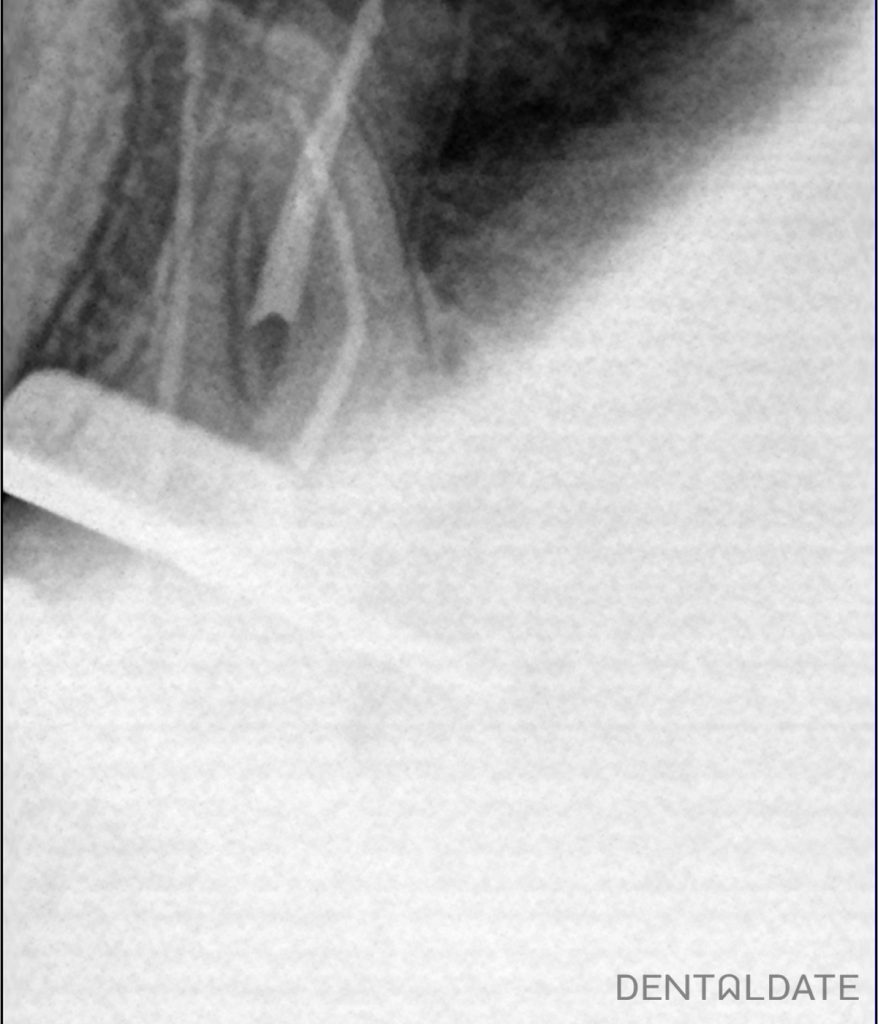

The old filling was removed. Access to the root canals was created. The root canals were unsealed. Calcium hydroxide was placed in the canals for 2 weeks for the purpose of disinfection inside the root structure.

After 2 weeks the canals were mechanically and medically prepared for obturation and filled by the method of hot condensation of gutta-percha and siler AH plus. Filling.